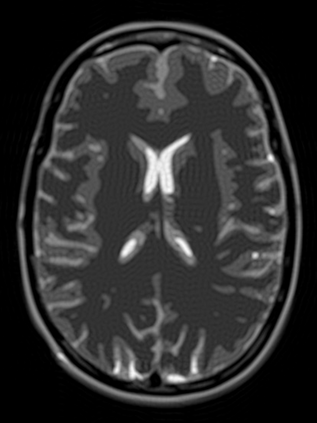

Implicit neural representations (INRs) have emerged as a powerful tool for solving inverse problems in computer vision and computational imaging. INRs represent images as continuous domain functions realized by a neural network taking spatial coordinates as inputs. However, unlike traditional pixel representations, little is known about the sample complexity of estimating images using INRs in the context of linear inverse problems. Towards this end, we study the sampling requirements for recovery of a continuous domain image from its low-pass Fourier coefficients by fitting a single hidden-layer INR with ReLU activation and a Fourier features layer using a generalized form of weight decay regularization. Our key insight is to relate minimizers of this non-convex parameter space optimization problem to minimizers of a convex penalty defined over an infinite-dimensional space of measures. We identify a sufficient number of samples for which an image realized by a width-1 INR is exactly recoverable by solving the INR training problem, and give a conjecture for the general width-$W$ case. To validate our theory, we empirically assess the probability of achieving exact recovery of images realized by low-width single hidden-layer INRs, and illustrate the performance of INR on super-resolution recovery of more realistic continuous domain phantom images.